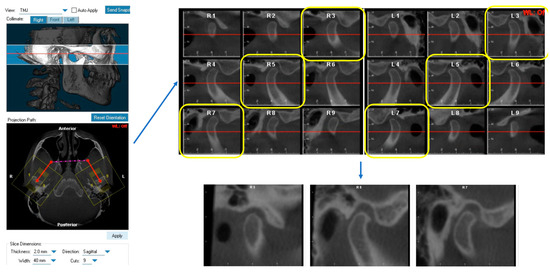

2.2. CBCT Measurements

All CBCT images were oriented and analyzed using the Dolphin Imaging 3D software (version 11.9, Dolphin Imaging & Management Solutions, Chatsworth, CA, USA). Each head was oriented in three planes of space for frontal and lateral views. The head was oriented in the frontal view with the floor of both orbits parallel to the floor [16]. In the right-side lateral view, the head position was adjusted so that the glabella was used to define the distance from the facial axis point of the maxillary central incisor to the goal anterior limit line (GALL) line matched to the clinical record. The lateral borders of the orbital rim, ramus borders, and mandibular angles were superimposed to the best fit from left and right. After orientation, the axial image demonstrating the largest mediolateral dimension of the condyle was selected. Then, we drew the reference line connecting the medial and lateral poles of the condyle [17]. Nine sagittal TMJ slices were made with 2.0 mm thickness for each joint. The 3rd, 5th, and 7th cuts from the right TMJ were saved as the lateral, central, and medial pole and the 3rd, 5th, and 7th cuts from the left TMJ were saved as the medial, central pole, and lateral pole, respectively (Figure 1). Three linear measurements of TMJ space, including the anterior joint space (AS), superior joint space (SS), and posterior joint space (PS), were performed on each cut as previously described [13]. Briefly, the distance from the most superior point of the condyle to the most superior aspect of the glenoid fossa was measured as the superior joint space (SS). Lines tangent to the most anterior and posterior aspects of the condyle were drawn from the most superior aspect of the glenoid fossa. The shortest distances from the anterior and posterior tangent points to the glenoid fossa were measured as the anterior joint space (AS) and posterior joint space (PS) (Figure 2).

Figure 1. Generation of sagittal TMJ slice cuts from CBCT.